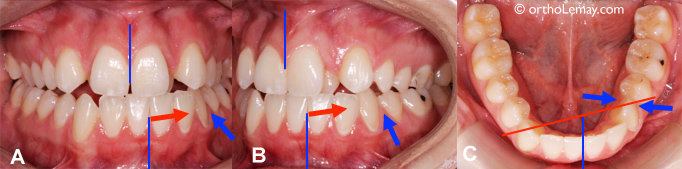

Exemple de la fermeture d’un diastème entre des incisives centrales supérieures à la suite de l’éruption des canines permanentes. (A) À l’âge de 8.9 ans, ce garçon présente un diastème important et un frein labial qui s’attache entre les incisives centrales. (B) Près de 5 ans plus tard (13.5 ans), les canines permanentes sont sorties et ont contribué à fermer le diastème en déplaçant les incisives vers le centre. Aucune frénectomie n’a été faite.